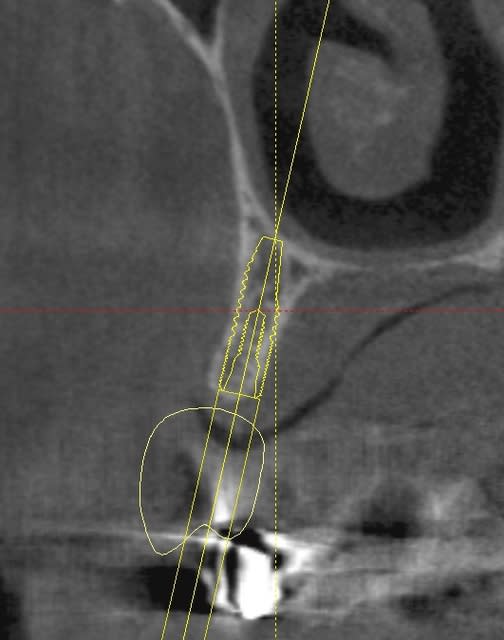

une petite étude de ton cas avec implants osseosped Astra :

12 : 3.5 x 11

13 : 3 x 11 (?)

14 : 3 x 11 (?)

15 : 3.5 x 11 (?)

16 : 4 x 11

17 : 4 x 11

je ne pratique pas donc pas de conseils sur ces implants.

techniquement:

extraction de 12 , curetage soigneux.

vue la qualité osseuse :

si D4 :

saignée à la lame n°15

si D3 :

avec un disque diamanté 10 x 0.3mm incision crestale de 12 à 16 ou 17

puis avec un disque de 20x0.3mm ou à la lame 15 approfondissement de la saignée

puis expansion en "douceur" (sans incision de décharge verticale, à priori car la ligne de crête est relativement droite)

pose de tes implants et dans ce cas, le VitalOs me semble idéal.

la difficulté majeure sera la corticale palatine qui ne semble pas géniale et qui méritera une attention particulière, ostéotome de Tatum +++

honnêtement je ne commencerais pas par un cas comme celui ci sans une solide connaissance de la sensibilité osseuse.

pas de provisoire